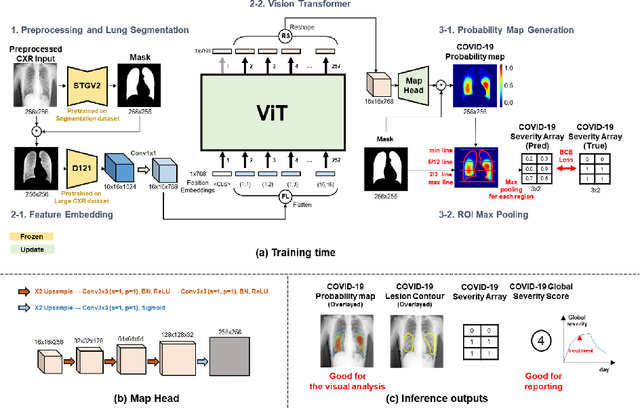

Abstract:Under the global pandemic of COVID-19, building an automated framework that quantifies the severity of COVID-19 and localizes the relevant lesion on chest X-ray images has become increasingly important. Although pixel-level lesion severity labels, e.g. lesion segmentation, can be the most excellent target to build a robust model, collecting enough data with such labels is difficult due to time and labor-intensive annotation tasks. Instead, array-based severity labeling that assigns integer scores on six subdivisions of lungs can be an alternative choice enabling the quick labeling. Several groups proposed deep learning algorithms that quantify the severity of COVID-19 using the array-based COVID-19 labels and localize the lesions with explainability maps. To further improve the accuracy and interpretability, here we propose a novel Vision Transformer tailored for both quantification of the severity and clinically applicable localization of the COVID-19 related lesions. Our model is trained in a weakly-supervised manner to generate the full probability maps from weak array-based labels. Furthermore, a novel progressive self-training method enables us to build a model with a small labeled dataset. The quantitative and qualitative analysis on the external testset demonstrates that our method shows comparable performance with radiologists for both tasks with stability in a real-world application.